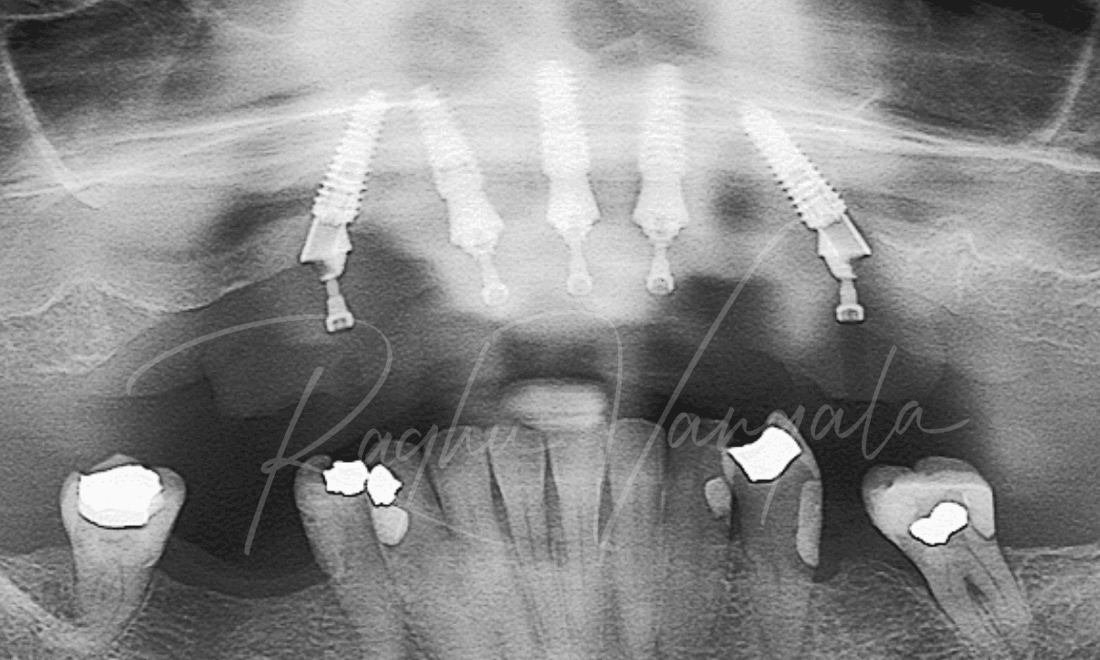

This lovely lady came to us wanting options to have a beautiful smile again. She had a partial upper plate and a few teeth left on her upper jaw. She wasn't a fan of her partial plate as it didn't feel right in her mouth. Her options for her upper teeth were to either get an upper denture or get implants and get a fixed denture. She decided to go with the permanent option, this consisted of getting her remaining upper teeth out and placing 5 implants. We then placed her upper denture a week later. She is very happy with the results and is now smiling like she was when she was younger.